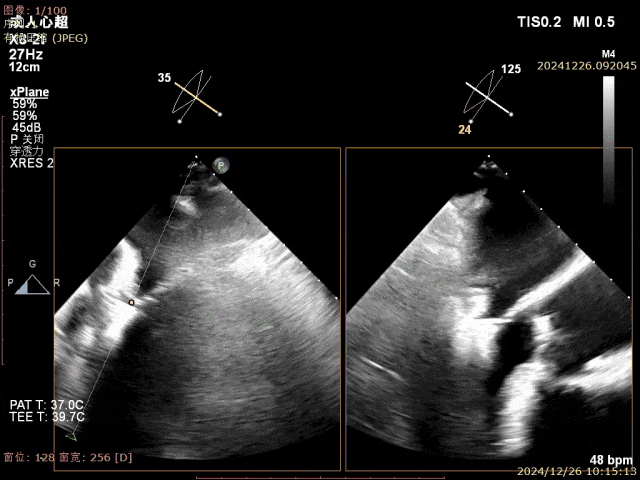

患者为68岁男性,3月前出现气短,活动后明显,休息可缓解,无明显胸痛,无夜间呼吸困难,就诊当地医院考虑“肺炎、心衰”,给予对症治疗好转,具体不详,无明显发热,无咳嗽咳痰,出院后未规律服药。10天前,气短再发,就诊当地医院心脏彩超提示二尖瓣后叶腱索断裂,二尖瓣关闭不全伴重度反流。左心增大,室间隔增厚,肺动脉高压,三尖瓣轻度反流,主动脉瓣中度反流。心电图提示房颤,左室肥大。为进一步诊治入院。经食道超声提示:患者二尖瓣后叶脱垂伴腱索断裂,前叶2.6cm,后叶1.4cm,脱垂宽度16mm,脱垂高度8mm,瓣口面积6.0cm²。

术前影像